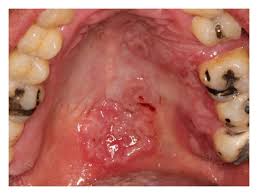

• the diagnosis of syphilis is made based on clinical signs and symptoms, microscopic examination and serologic tests. (2)department of ophthalmology, king's college hospital, london, uk. Treatment will kill the syphilis bacterium and prevent further damage, but it will not repair damage already done. Three of these types of sore are, by virtue of their name and location, frequently confused—cold sores caused by oral herpes, canker sores, and chancre sores caused by syphilis. Syphilis is a highly infectious sexually transmitted infection (sti) caused by bacteria, which is usually spread through vaginal, anal, or oral sex. Syphilis is a sexually transmitted disease that presents itself with symptoms such as a sores, fever, weight loss and tiredness. This lesion occurs at the site of inoculation. Syphilis is transmitted by direct contact with a syphilis sore, which is a painless ulcer known as a chancre. People can experience an array of sores on their mouths and their genitals. Syphilitic chancre is a solitary, painless, indurated, reddish ulcer, accompanied by regional lymphadenopathy (1), which is localized at the site of treponema pallidum (tp) inoculation and usually resolves after approximately one month (1). Syphilis infection progresses in three stages, oral syphilis is identified by cold sores also known as chancres around the oral cavity. • medical practitioners should consider secondary syphilis in the differential diagnosis of white and ulcerative oral lesions. Stds also have the potential to affect the oral cavity and cause mouth sores.

Syphilis is a sexually transmitted bacterial infection of the spirochete, treponema pallidum. These lesions are often associated with submandibular and cervical lymphadenopathy. Syphilis is a sexually transmitted infection caused by the bacterium treponema pallidum subspecies pallidum. Without treatment, syphilis can move to the next stage. What types of stds cause symptoms in mouth? Saline rinses and a corticosteroid oral gel were ineffective. I got a very painful ulcer ( white in the middle,, probably 1 or 2 mm in size ) situated just beneath the gum, lower teeth (inner side of gums, not outside adjacent to lips) and not on my lips, tongue or palate, which i have seen. Über 7 millionen englischsprachige bücher. These open sores usually heal and go away within 3 to 6 weeks. Thakrar p (1), aclimandos w (2), goldmeier d (3), setterfield jf (1) (4). • medical practitioners should consider secondary syphilis in the differential diagnosis of white and ulcerative oral lesions. Syphilitic chancre is a solitary, painless, indurated, reddish ulcer, accompanied by regional lymphadenopathy (1), which is localized at the site of treponema pallidum (tp) inoculation and usually resolves after approximately one month (1). Nearly 115,000 new cases of syphilis have been diagnosed in the year 2018 alone, as per the centers for disease control and prevention (cdc) reports.

During the first stage of infection, syphilis may appear as sores, known as chancres, on your lips, the tip of your tongue, your gums or at the back of your mouth near your tonsils. Thakrar p (1), aclimandos w (2), goldmeier d (3), setterfield jf (1) (4). Sir, primary syphilis is characterized by a chancre appearing between 10 and 90 days after infection (1). Syphilis is a bacterial infection usually spread by sexual contact. Because these sores are often painless, many people never notice them. Primary syphilis is detected as ulcer in all patients, while secondary syphilis is detected as ulcer in about 50% of cases. Chancres can occur on or around the external genitals, in the vagina, around the anus, or in the rectum, or in or around the mouth. Three of these types of sore are, by virtue of their name and location, frequently confused—cold sores caused by oral herpes, canker sores, and chancre sores caused by syphilis. Could my mouth ulcer be syphilis ? It is not common to give or receive oral. While primary syphilis often involves genitalia, oral manifestations are observed in a subset of patients. Stds also have the potential to affect the oral cavity and cause mouth sores. Syphilis spreads from person to person via skin or mucous membrane contact with these sores.